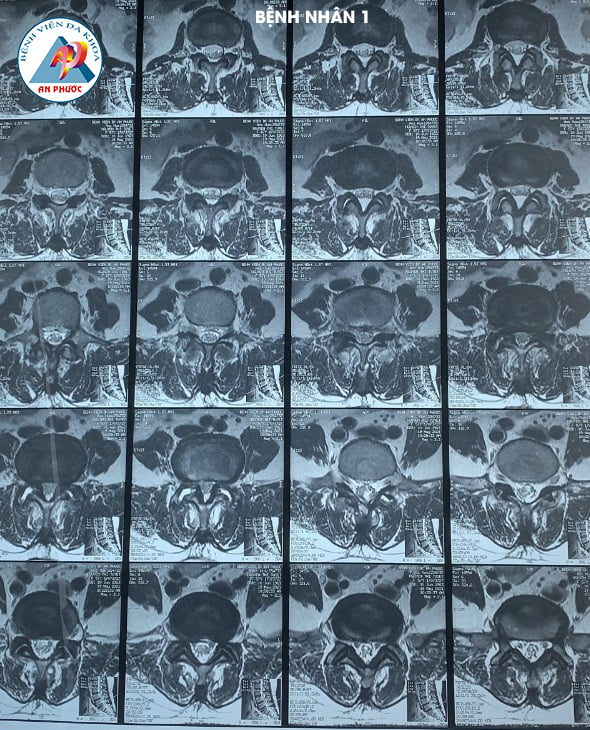

Trường hợp 1: Bệnh nhân nữ, 58 tuổi, ngụ tại Hàm Thuận Nam, Bình Thuận. Vào viện trong tình trạng đau lưng, tê, yếu hai chân hơn 10 năm. Bệnh nhân đã được điều trị nội khoa, kết hợp với tập vật lý trị liệu nhiều lần, ở nhiều Bệnh viện khác nhau, nhưng bệnh không giảm.

Sau khi được Bác sĩ chuyên khoa khám lâm sàng và cận lâm sàng (chụp MRI, XQ CSTL (có Film). Bệnh nhân được chỉ định phẫu thuật: Lấy nhân đệm và làm cứng CSTL bằng nẹp vis, thay đĩa đệm nhân tạo.